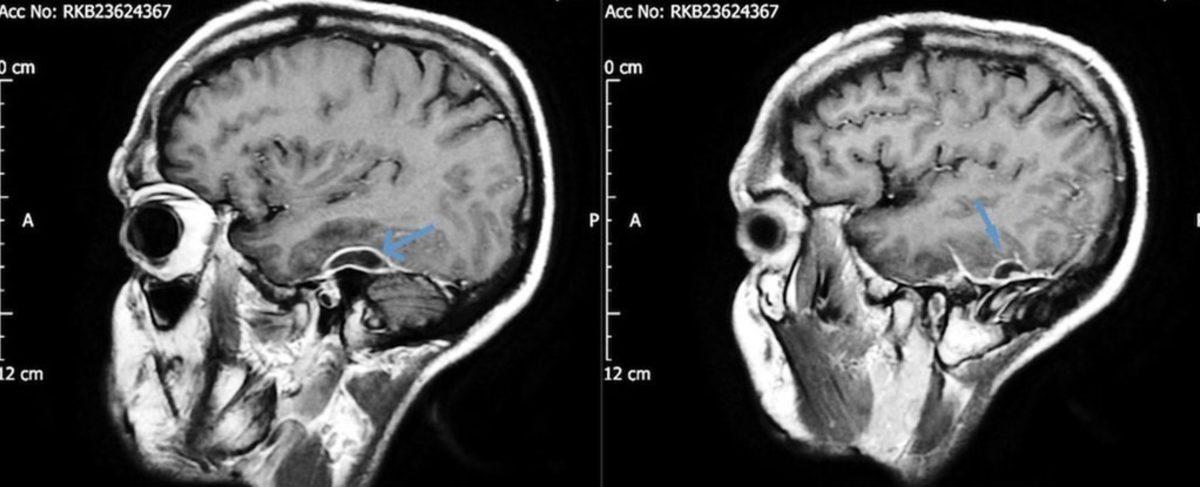

Rapor edilen vakaya göre 31 yaşında, sağlıklı görünen bir adam aniden yere yığıldı ve ambulansla hastanenin acil servisine götürüldü. Hastanede birtakım nöbetler geçiren adam, oldukça uykulu ve kafası karışıktı. İlerleyen günlerde baş ağrısı ve bulantı tecrübeleyen adamın hafızası da eskisi kadar güçlü değildi. Daha sonrasında yıllardır aralıklı şekilde sol kulak ağrısı çektiğini ve duyma kaybı yaşadığını bildiren adamın tehlikeli bir enfeksiyon kaptığı anlaşıldı. Yapılan CT tarama testleri sonucunda adamın kafatasında iltihap dolu bir apse bulundu.

Kulak çubuğunun pamuğu, adamın kulağına sıkıştı. Kanalları tıkayan pamuk sadece ses kaybına ve ağrıya yol açmadı; aynı zamanda kulak kirinin de içeride birikmesine neden oldu. İlerleyen ve gittikçe büyüyen kir sonunda beyni saran dokuya ulaştı ve burada iltihaba neden oldu.